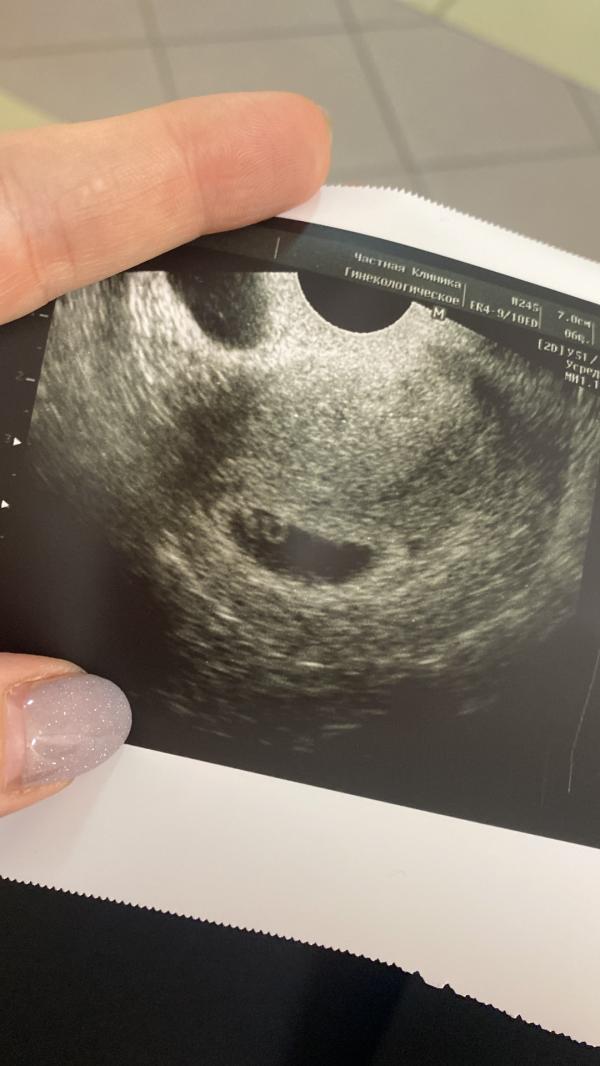

Сходила на узи, расстроенная. СБ не включили, сказала есть, но слабое. Теперь переживаю. Еще написали структура матки неоднородная, я уже погуглила что это плохо. Кто разбирается посмотрите УЗИ(второе фото) что-то я вообще в таком состоянии, аж плакать хочу. 😒 И еще кто знает для рубца 7мм это норм?